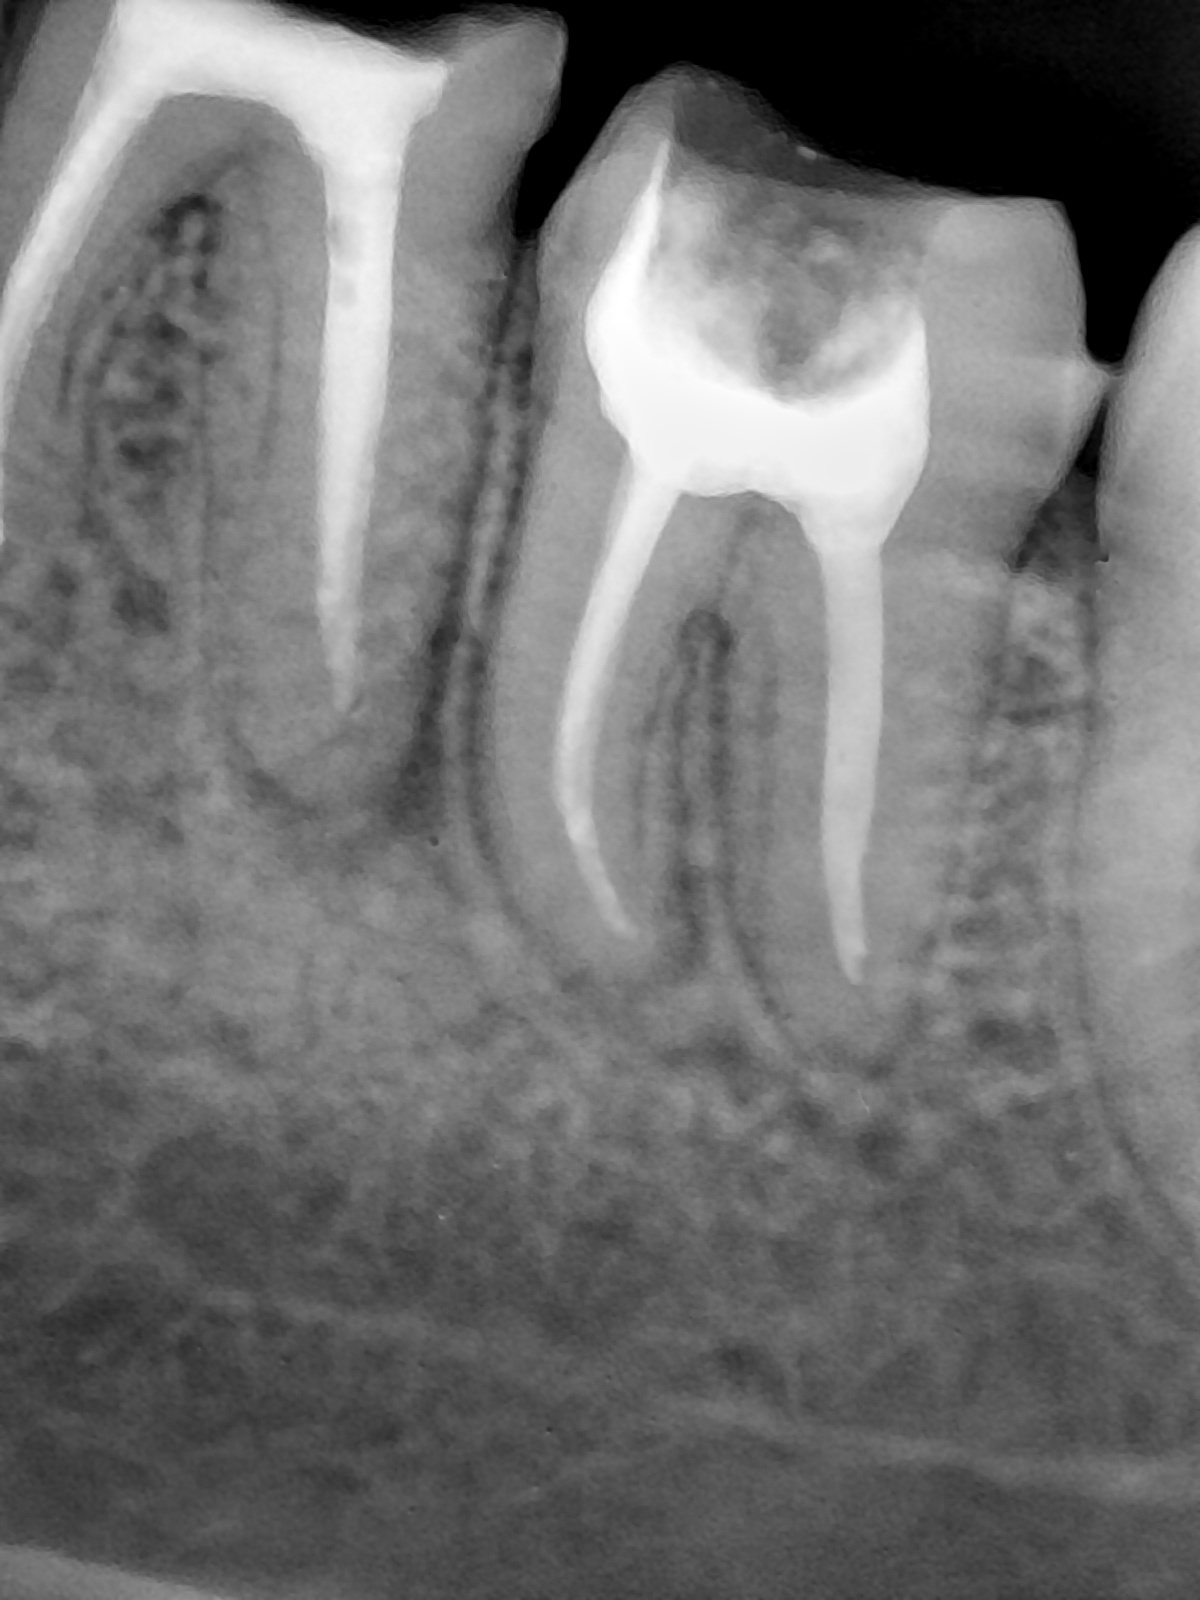

CR/DR 牙齿分割阶段记录

当前进展

- 完成了 CR/DR 牙齿相关分割训练

- 当前结果已经达到阶段预期,但仍有细节问题需要继续处理

相关测试

遇到的问题

- 训练过程中出现过 mask 下移问题

- 部分结果会出现 box 填充异常

- mask 边缘仍然有比较明显的锯齿感

参考